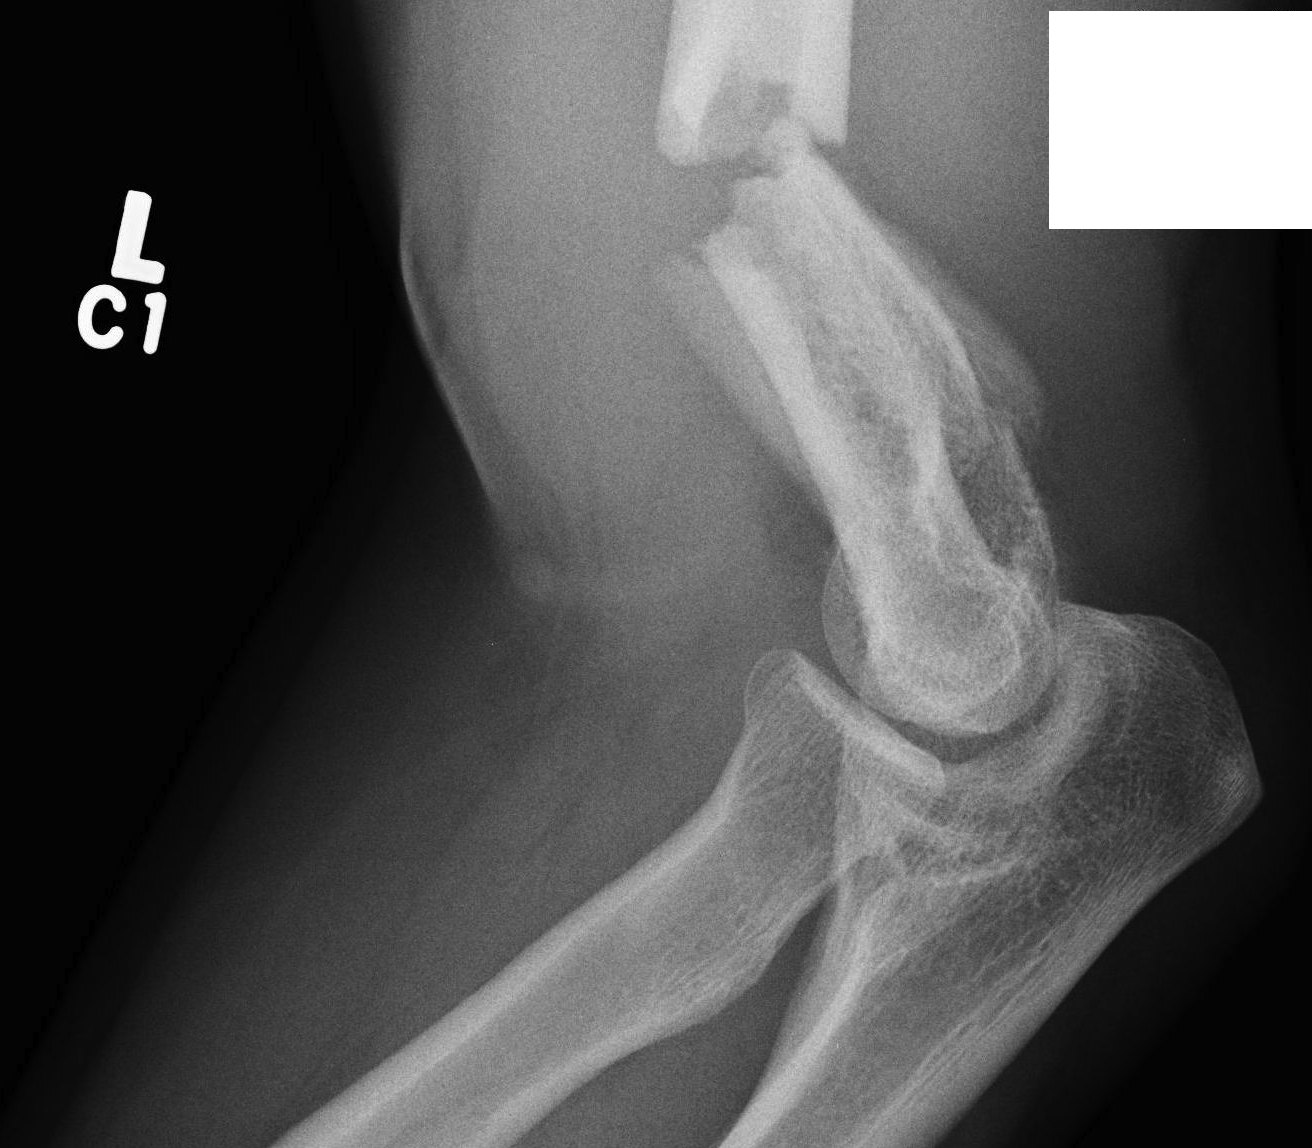

Olecranon Osteotomy

Indication

Complex intra-articular fractures

Technique

AO foundation surgery reference Chevron osteotomy

Chevron

- distally based V shaped

- through bare area of olecranon / smallest width of greater sigmoid notch

- 3 cm from tip

Fixation

- TBW v plate v intramedullary screw

Results

- systematic review of olecranon osteotomy and paratricipital approach

- longer operative time and higher incidence of infection with osteotomy

- no difference in outcome / ROM / hetertopic ossification / ulnar nerve injury

Coles et al J Orthop Trauma 2006

- 67 intra-articular fractures treated with olecranon osteotomy

- no nonunions

Somerson et al Should Elbow 2022

- 63 patients

- 14% wound dehiscence or infection

- 10% symptomatic hardware

- olecranon osteotomy increased re-operation rate